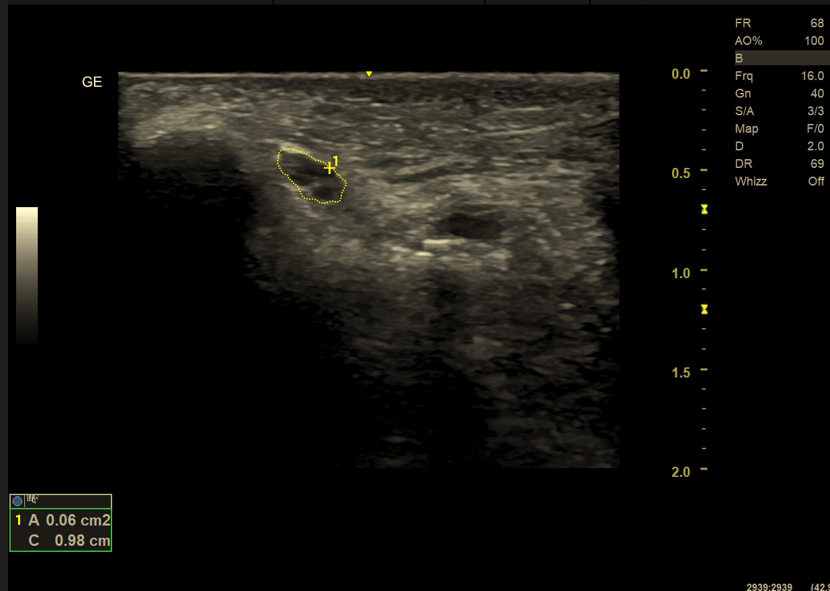

1. Zwiększenie pola przekroju poprzecznego nerwu (CSA)

Jednym z najbardziej obiektywnych i powtarzalnych parametrów w ultrasonografii nerwów jest pole przekroju poprzecznego nerwu (CSA – cross-sectional area). W warunkach prawidłowych wartości te mieszczą się w określonych normach, zależnych od lokalizacji anatomicznej oraz budowy pacjenta.

Patologiczne powiększenie CSA obserwuje się najczęściej w:

• zespołach uciskowych (np. cieśń nadgarstka, kanał łokciowy),

• neuropatiach zapalnych i demielinizacyjnych,

• obrzęku nerwu w przebiegu urazu lub przeciążenia.

Istotnym elementem badania jest porównanie nerwu z odcinkiem referencyjnym (proksymalnym lub dystalnym) oraz z nerwem po stronie przeciwnej, co zwiększa czułość diagnostyczną badania.